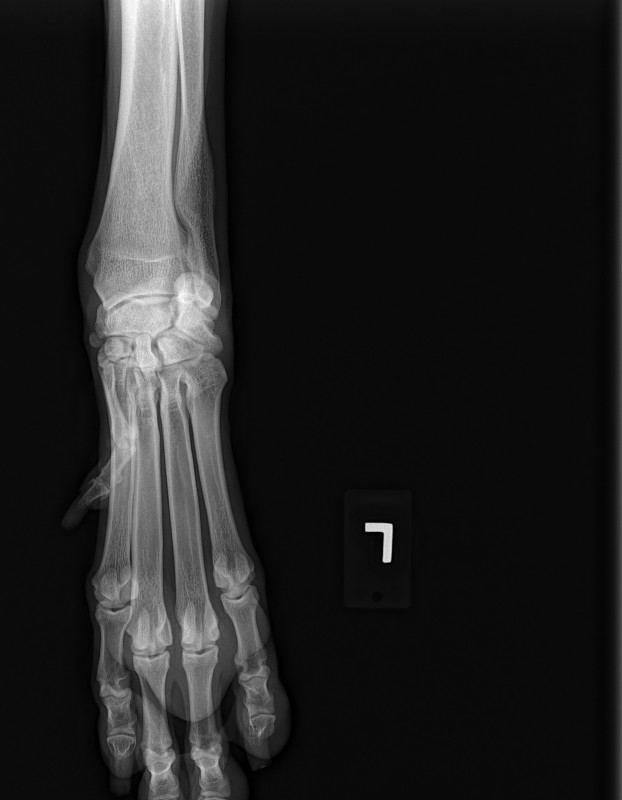

The current size of his mass is 8.2 cm x 10 cm x 21 cm. This is an extremely RARE cancer – less than 1%.

To further complicate matters, this mass has herniated down into his thigh and groin severely compromising his ureter and femoral nerve. He has had three CT scans of which his latest has shown that to date his chest remains clear of metastasis and his lymph nodes are not enlarged. His MRI has shown that his case is extremely complicated and the surgery he shall specifically require, scheduled for March 23rd has ONLY ever been done twice before by the two expert surgical oncologists assigned to him.